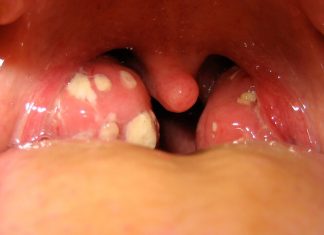

Tıkayıcı bademcik büyümesi apne (nefes tutma) veya büyüme-gelişme geriliği ile birlikte... Bademcikte tekrarlayan kanama tekrarlayan...